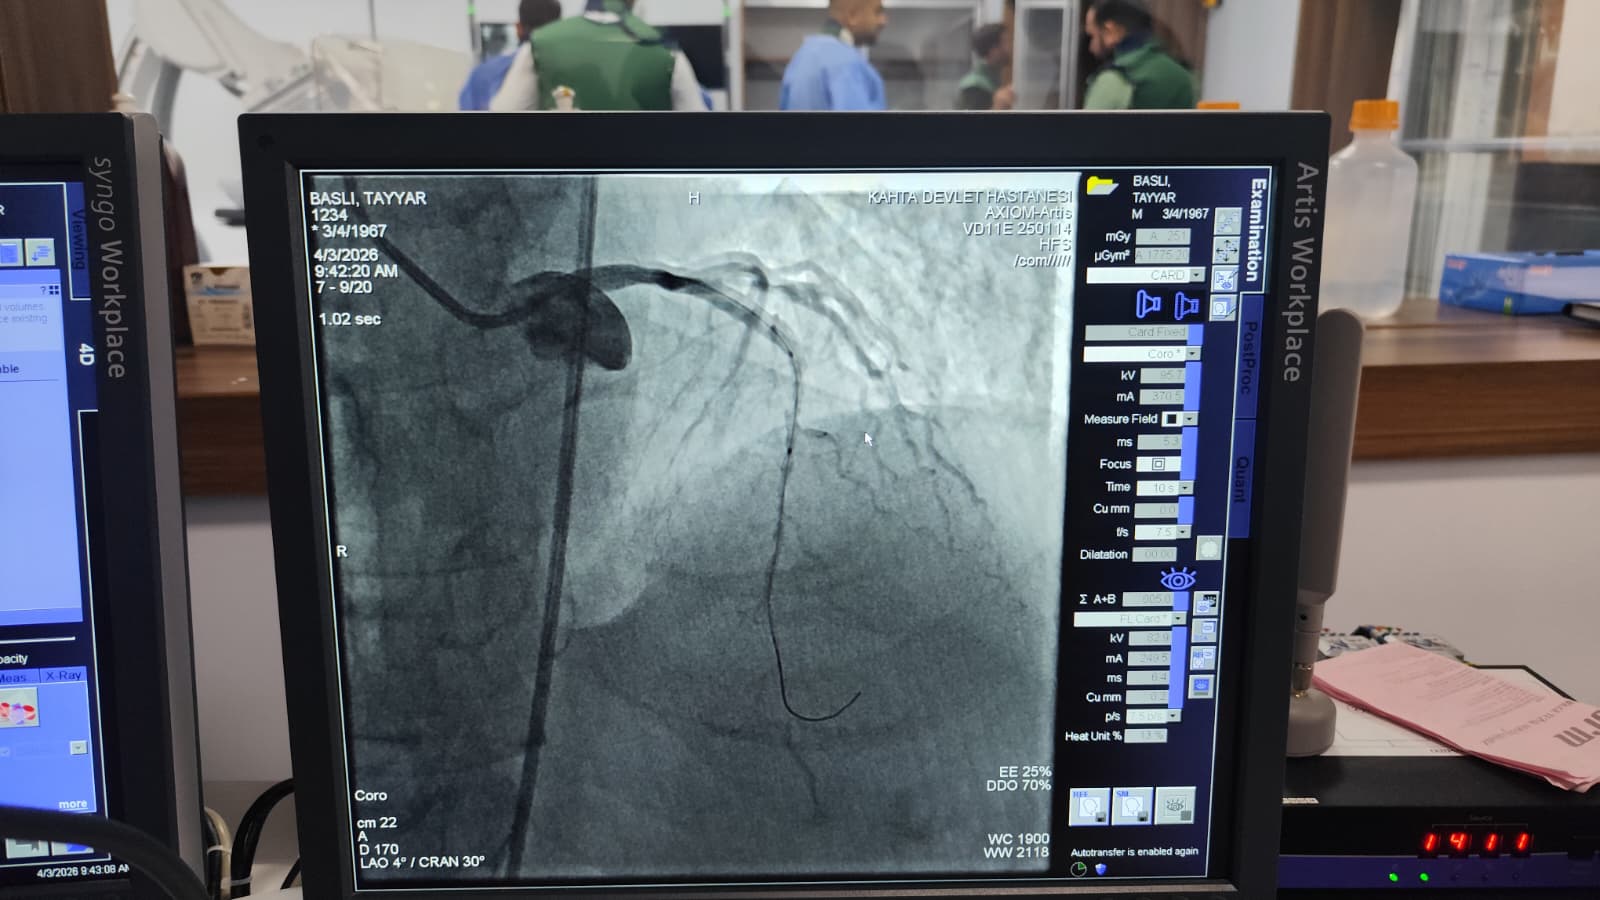

Kalp krizi şüphesiyle Kâhta Devlet Hastanesi Acil Servisi’ne başvuran hasta, yapılan ilk müdahalenin ardından vakit kaybetmeden anjiyo ünitesine alındı. Burada gerçekleştirilen operasyonla hastanın kapalı olan iki damarına stent takıldı. Müdahalenin ardından hastanın genel sağlık durumunun iyi olduğu öğrenildi.

Kâhta Devlet Hastanesi Başhekimi Dr. Mustafa Akel, “Hastanemizden 45 km mesafede ikamet eden 59 yaşındaki hastamız, göğüs ağrısı şikâyeti ile hastanemize başvurmuştur. Yapılan tetkiklerde kalp krizi geçirdiği tespit edildi ve acil bir şekilde yeni açmış olduğumuz anjio merkezimize hastayı aldık. Yapılan görüntülemede kalbinin ön damarı olan LAD mid bölgesi total tıkalı tespit edildi. Hastamızın kalbinin ön damarına iki adet Stent takarak tam açıklık sağlandı. Hastamızın genel durumu iyi olup yoğun bakıma takip amacıyla alındı.” dedi.